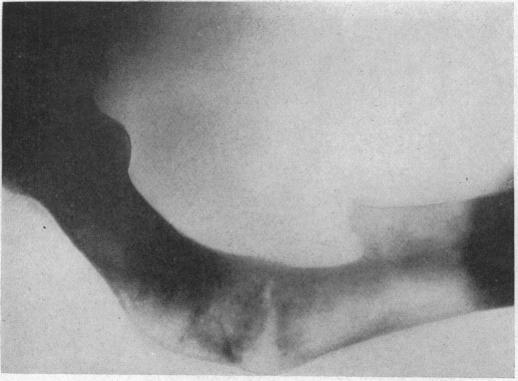

I. Benign Bone Cysts, Ostitis Fibrosa, Giant-Cell Sarcoma and Bone Aneurism of the Long Pipe Bones: A Clinical and Pathological Study with the Conclusion that Conservative Treatment is Justifiable.

Ann Surg. 1910 Aug;52(2):145-85. doi: 10.1097/00000658-191008000-00001.